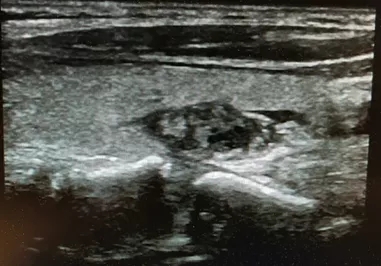

图1 甲状腺良性结节消融前横切位 42×20×18mm

图2甲状腺良性结节消融术后1月 35×17×15mm

女性,30岁,发现右侧颈部包块1年余入院。

查体:右侧甲状腺可触及大小4cm左右包块,质地韧,可以随着吞咽上下活动,无明显压痛。

彩超:右侧甲状腺内可见大小42×20×18mm实性包块。

术前细胞学穿刺:结节性甲状腺肿。